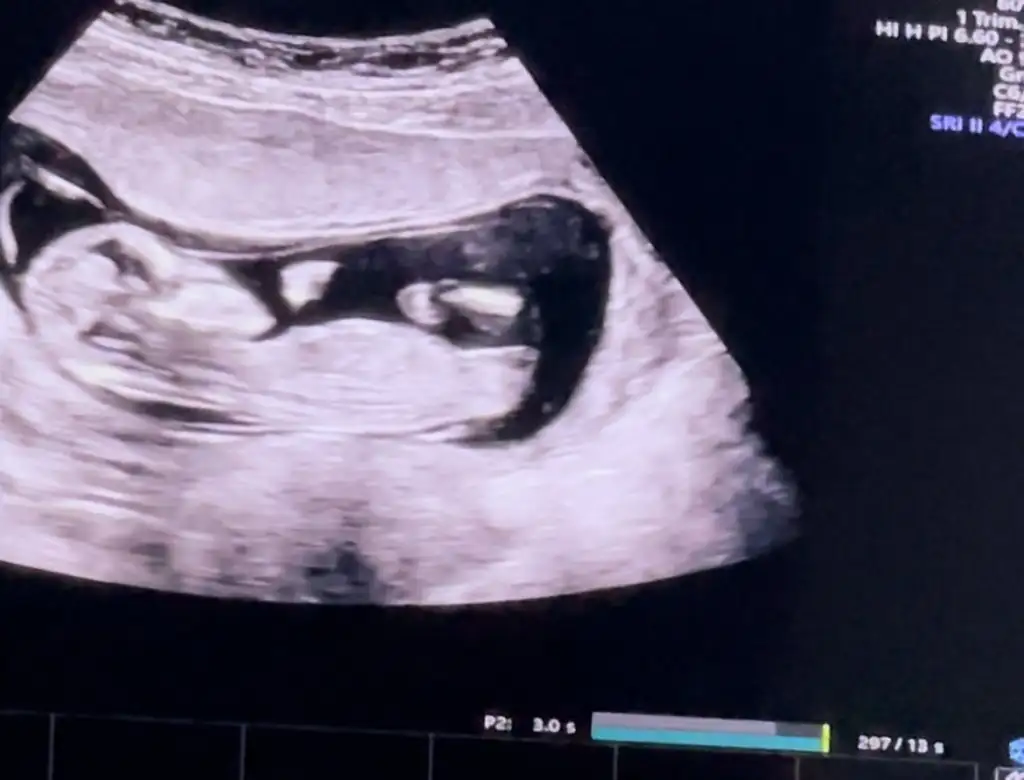

Kızlar 12+2 olduk, doktor %80 erkek dedi ama bazen kız olunca da vajina kısmı ödemden şişiyormuş ama yine de büyük ihtimalle erkek dedi, sizin tahminleriniz neler yardımcı olursanız çokk sevinirim

Yok canım en net görüntüleri attım zaten başka da görüntü vermediler. %80 erkek dedi kız olma ihtimali düşük o da bazen organ bölgesi ödemli olabiliyor ama büyük ihtimalle erkek dedi, zaten kızlarda genelde 3 çizgi oluyormuş sanırım sonradan duydum ben de bizde çizgi falan yok dikkatlice bakınca